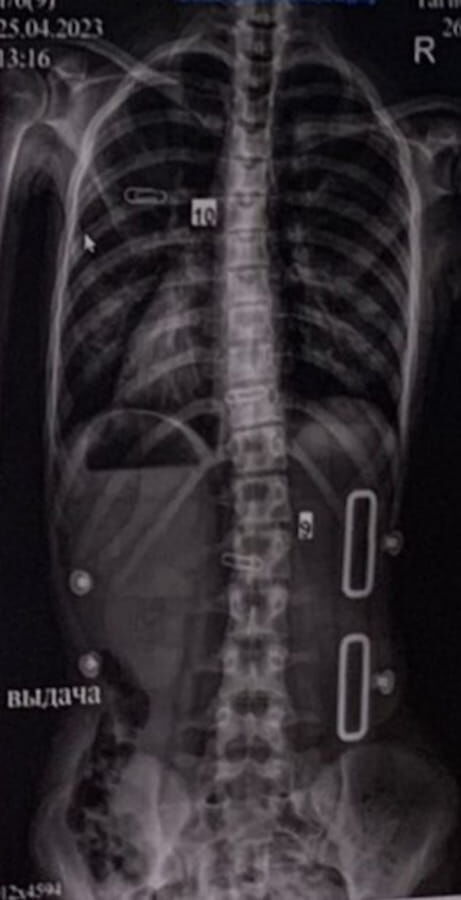

Результат коррекции при использовании корсета Шено и комплексов ЛФК по К.Шрот и ОКS